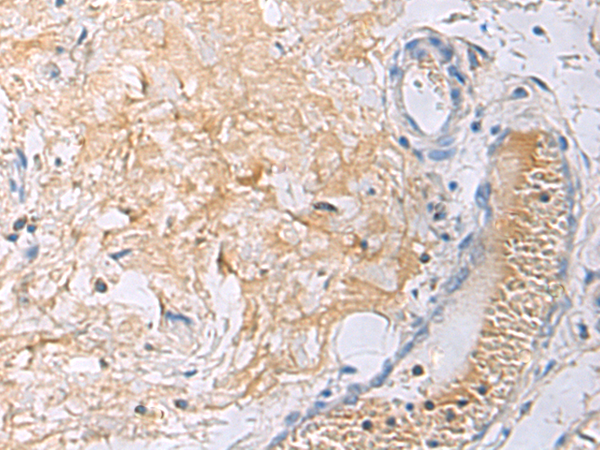

图片:

The image is immunohistochemistry of paraffin-embedded Human thyroid cancer using (HIC1 Antibody) at dilution 1/55.

,

The image is immunohistochemistry of paraffin-embedded Human gastric cancer using (HIC1 Antibody) at dilution 1/55.